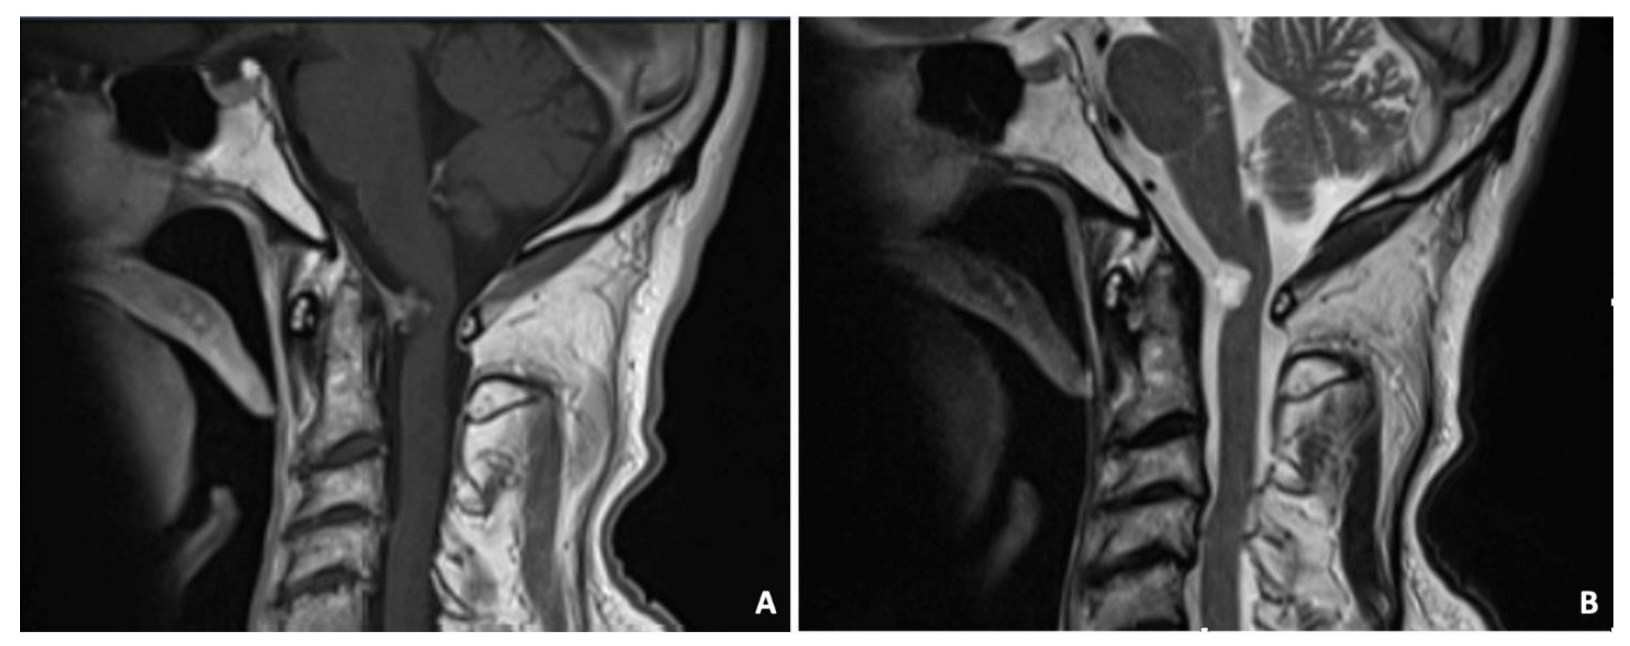

3.8. Case 8—Ganglion Cyst

3.9. Case 9—Histiocytic Sarcoma

| # 8 | 75 | M | Right upper limb weakness | C1 hemilaminectomy | Resection | Ganglion cyst | None | None | 3 years | Alive without disease |

| # 9 | 47 | F | Neck pain | FLA | Resection and CVJ stabilization | Histiocytic sarcoma | None | Yes | 9 months | Alive |